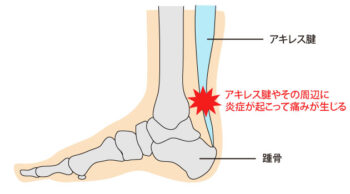

アキレス腱炎

アキレス腱炎は、腱に繰り返し負荷がかかることで炎症が起こる状態です。

・初期は軽い違和感や張り感から始まり、悪化すると歩行や運動時に痛みが強くなる

・運動後に腱の腫れ・熱感・硬さを感じることが多い

アキレス腱炎

・ふくらはぎやかかとの上部に痛み・張り感・腫れ

・運動時や運動後に痛みが増す

・腱の硬さや違和感が慢性的に続く